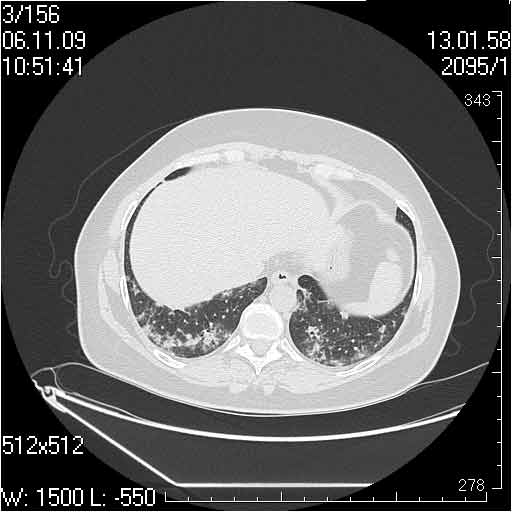

Случай №2

Мужчина 54 лет

Случай 2: картина патологических изменения довольно типична: GGOs & thickened interlobular septas = "crazy paving" sign. Наличие плотностей по типу матового стекла в сочетании с утолщением междолевых перегородок, даёт признак булыжной мостовой; на первом месте будет стоят диагноз альвеолярных протеиноз.